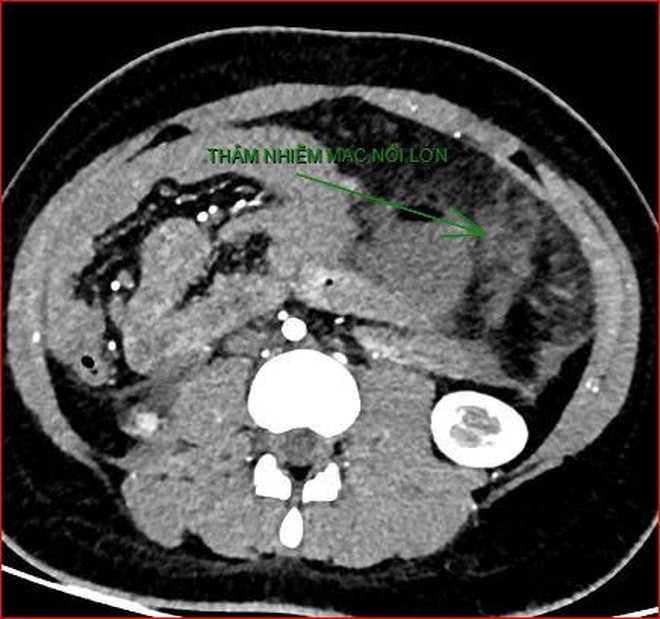

Khoảng 21 giờ 40, kết quả chụp CT cho thấy bệnh nhân rơi vào tình trạng cực kỳ nặng và hiếm gặp, bao gồm: xoắn dạ dày, nhồi máu thận trái, nhồi máu lách, viêm đầu tụy, viêm hỗng tràng, kèm dịch ổ bụng và tràn dịch màng phổi, trên nền bệnh nhân mắc hội chứng Down và tim bẩm sinh.

Hình ảnh chụp CT ổ bụng cho thấy dạ dày giãn lớn, xoắn bất thường; kèm tổn thương nhồi máu lách và viêm tụy trên nền ca bệnh hiếm, diễn biến đặc biệt nặng - Ảnh Bệnh viện cung cấp

Hình ảnh chụp CT ổ bụng cho thấy dạ dày giãn lớn, xoắn bất thường; kèm tổn thương nhồi máu lách và viêm tụy trên nền ca bệnh hiếm, diễn biến đặc biệt nặng – Ảnh Bệnh viện cung cấp